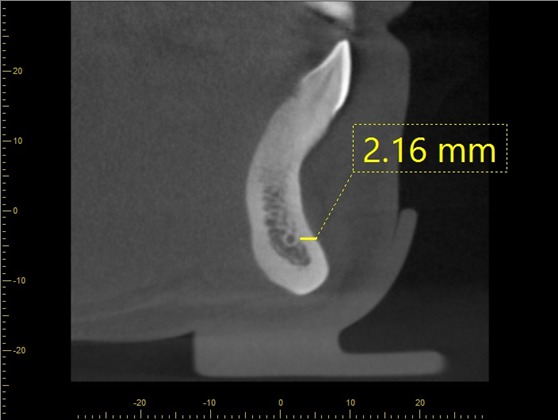

Methods: Retrospective study of 120 CBCT images in the anterior mandible were performed. All CBCT images were obtained with 3D Accuitomo (J. Morita Mfg. Corp., Kyoto, Japan) with the exposure setting of 80-90 kVp, 4-5 mA, 18 s., and FOV 10×10 cm with voxel size of 0.25 mm. The assessment of the visibility of the MIC will be recorded the detection frequencies and analyzed into the percentage. For linear measurement, the CBCT images will be analyzed from the curvedMPR. The cross-sectional images that pass through the midline, 5 mm, 10 mm, 15 mm, 20 mm from the midline (both right and left sides) will be selected and measured with the digital ruler from the viewer (i-dixel) equipped with the CBCT machine. All images will be measured in the following distances: Incisive canal to the inferior border of mandible (L1), Incisive canal to buccal plate of mandible (L2), Incisive canal to lingual plate of mandible (L3), Bucco-lingual diameter of outer contour of MIC (D1), Vertical diameter of outer contour of MIC (D2).

Results: The MIC was identified in 96% of the CBCT images. Mean (s.d.) distance from MIC to inferior border of mandible at midline, 5 mm, 10 mm, 15 mm, 20 mm from the midline were 8.74 (1.61) mm, 9.80 (1.37) mm, 10.21 (1.12) mm, 10.13 (1.89) mm, 11.03 (1.56) mm, respectively. Mean (s.d.) distance from MIC to buccal border of mandible were 4.17 (1.41) mm, 3.86 (1.28) mm, 3.74 (1.19) mm, 3.24 (1.03) mm, 3.18 (1.31) mm, respectively. Mean (s.d.) distance from MIC to lingual border of mandible were 4.02 (1.17) mm, 3.46 (1.06) mm, 3.54 (1.62) mm, 3.29 (1.47) mm, 3.84 (1.71) mm, respectively. Mean (s.d.) buccolingual diameter were 1.78 (0.37) mm, 1.97 (0.52) mm, 2.10 (0.40) mm, 2.25 (0.73) mm, 2.86 (0.51) mm, respectively. Mean (s.d.) vertical diameter were 1.84 (0.37) mm, 1.91 (0.49) mm, 2.53 (0.38) mm, 2.92 (0.46) mm, 3.11 (0.43) mm, respectively.